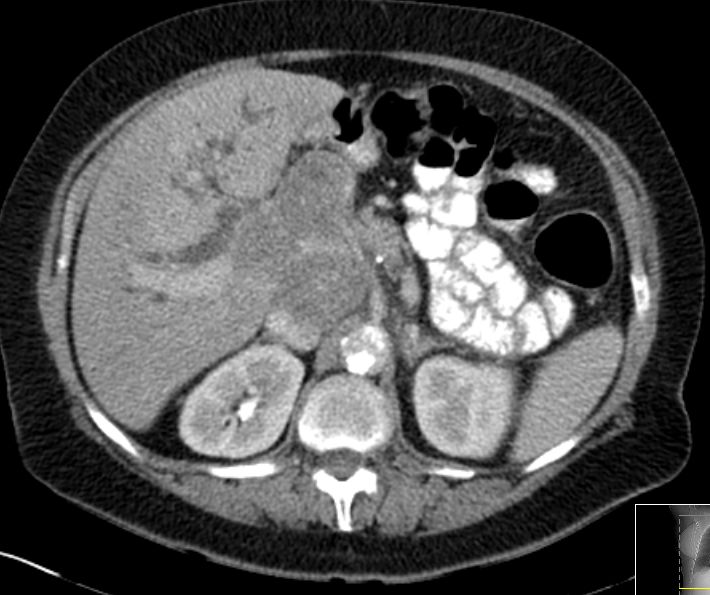

Leberhilus

69-jährige Frau, die mit Verschlussikterus eingeliefert wird. Im Leberhilus eine große Raumforderung. Erweierung der intrahepatischen Gallengänge. Seit einem Jahr chronischer Husten. Eine Untersuchung beim Lungenfacharzt ohne Befund. Nach ERCP und Stenteinlage Rückgang des Ikterus. Bronchoskopisch Nachweis eines kleinzelligen Tumors im rechten Unterlappenbronchus.